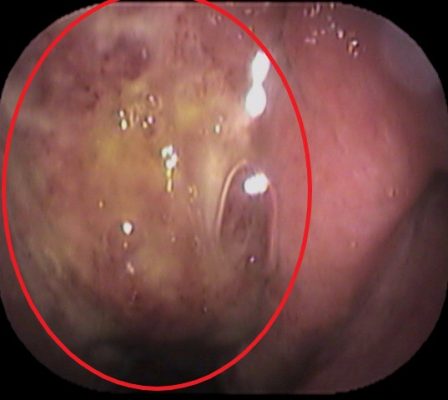

鼻からファイバーで鼻・ノドの奥をチェックします ![]()

上咽頭(赤丸部分) にも膿の付着と炎症を認めました(上咽頭炎)。